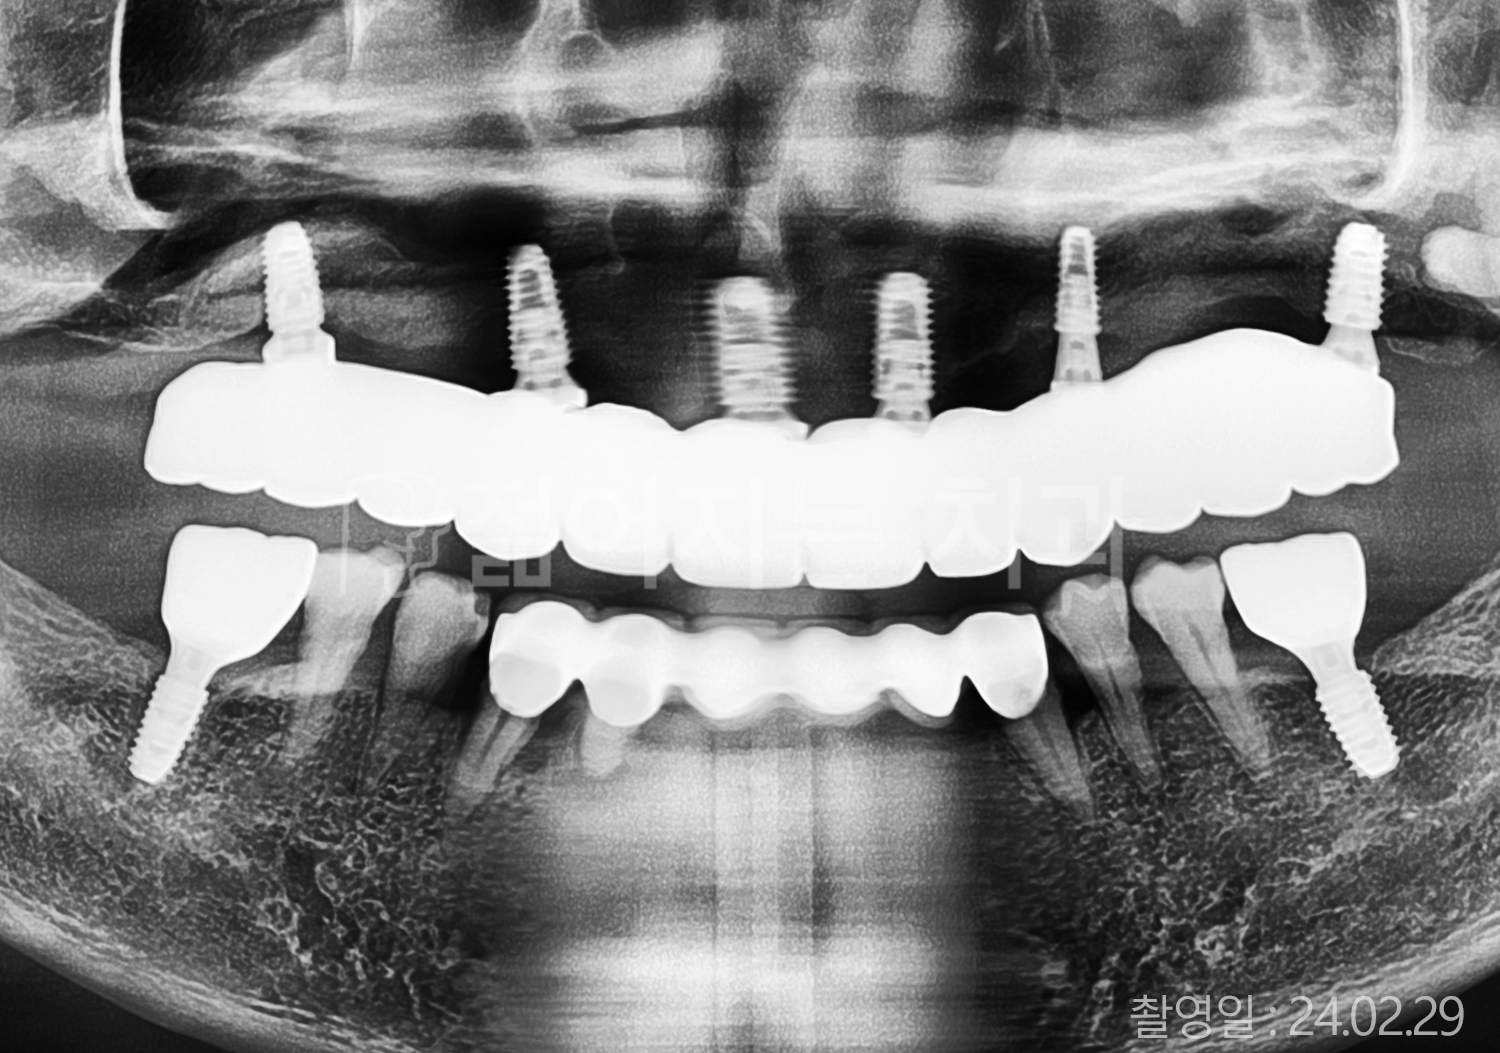

• 70대 당뇨 전체치아 10개 이상 임플란트

• 70대 고혈압, 당뇨 전체치아 10개 이상 임플란트